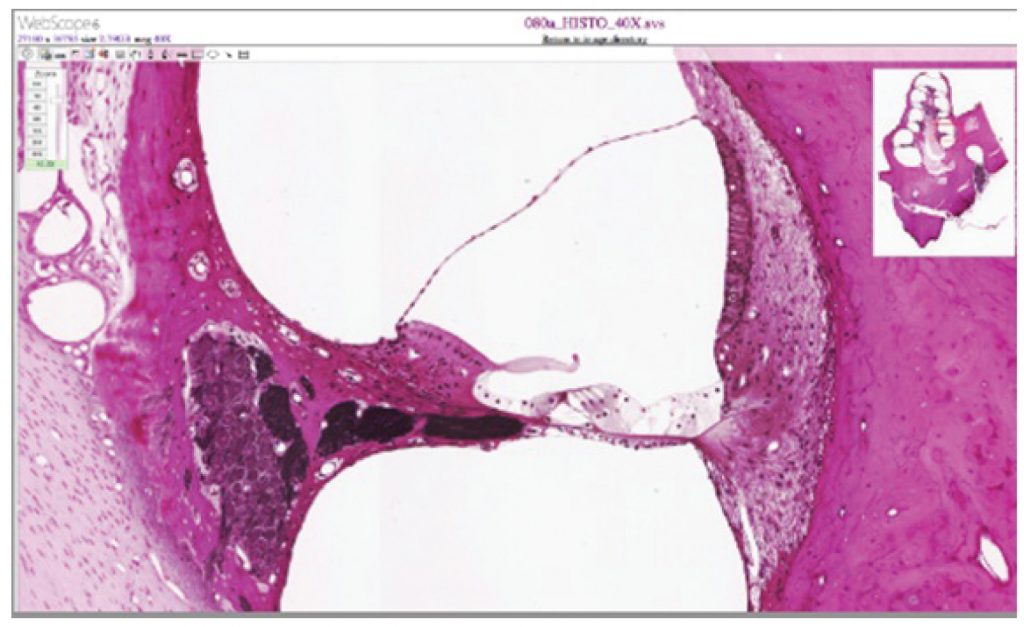

Cochlea and Organ of Corti

Figure 3.5 – Cochlea and Organ of Corti: LM Γ— 412. (Micrograph provided by the Regents of University of Michigan Medical School Β© 2012)